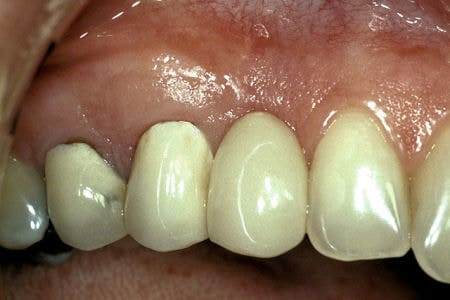

Before